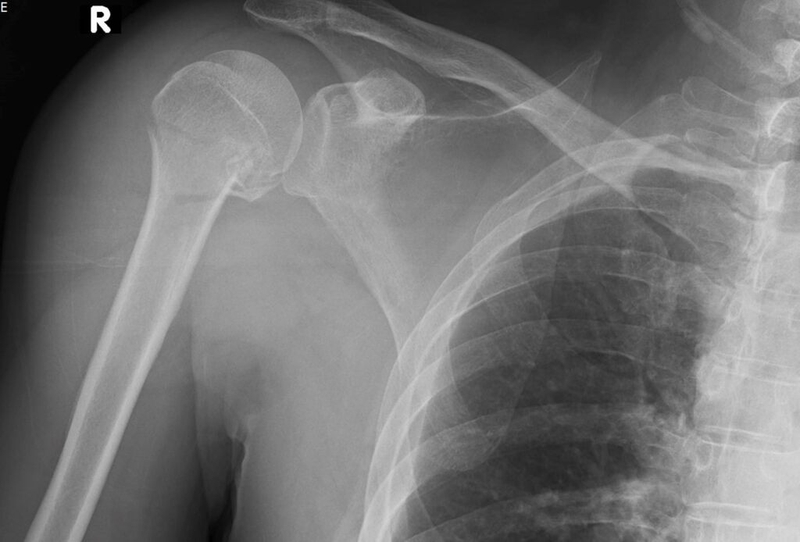

Theo các chuyên gia, khi trẻ nhỏ bị gãy xương, tỉ lệ tổn thương ở phần sụn tiếp hợp chỉ chiếm từ 10-15%, và rất hiếm khi xảy ra gãy vụn xương. Điều đặc biệt là ổ gãy xương ở trẻ có khả năng tự kích thích sự phát triển nhờ vào việc tăng cường lưu thông máu đến lớp sụn tiếp hợp. Vậy, vì sao xương trẻ nhỏ khi gãy lại mau liền hơn so với người lớn?

Xương của trẻ có cốt mạc liên tục và được cung cấp lượng máu dồi dào, điều này tạo điều kiện thuận lợi cho quá trình phục hồi. Càng nhỏ tuổi, tốc độ liền xương càng nhanh. Đối với trẻ sơ sinh, thời gian hồi phục chỉ khoảng 2 - 3 tuần; trẻ từ 7 - 10 tuổi mất khoảng 6 tuần; và trẻ trên 10 tuổi khoảng 8 - 10 tuần. Nhờ những đặc điểm này, trẻ nhỏ có khả năng hồi phục rất nhanh sau chấn thương xương.

Tình trạng gãy xương không liền xương ở trẻ nhỏ là rất hiếm gặp, thậm chí là không xảy ra (trừ một số trường hợp bị chấn thương rất nghiêm trọng như gãy xương hở, xương bệnh lý hoặc viêm xương). Vậy có những kiểu gãy xương nào ở trẻ em?